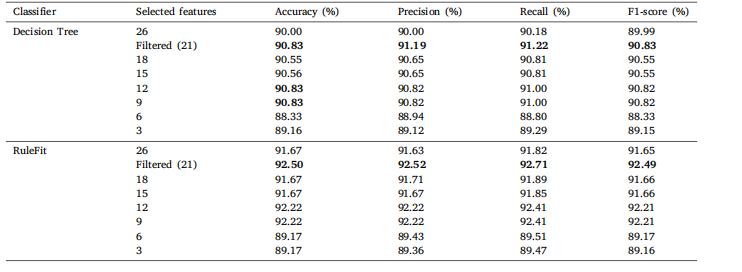

Table 7Classification results of COVID-19 Radiography Database on a comprehensive set of statistical features with varying feature counts for DT andRuleFit

表7 基于不同数量统计特征的COVID-19放射影像数据库分类结果(针对决策树(DT)和RuleFit模型)。

Table 8Classification results of Ultrasound Breast Images for Breast Cancer on a comprehensive set of statistical features with varying feature countsfor DT and RuleFit

表8 基于不同数量统计特征的乳腺癌超声图像分类结果(针对决策树(DT)和RuleFit模型)。